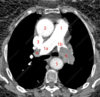

• Enfisema

• Neumotorax

How well did you know this?